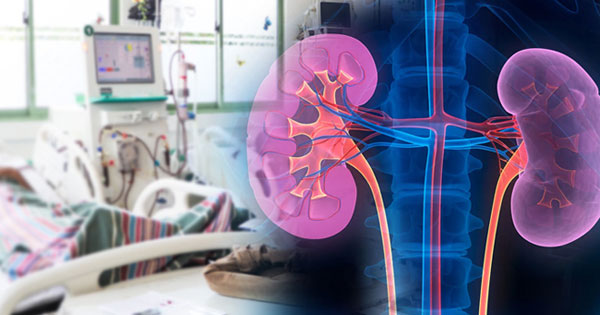

එපොයිටින් පෙර පුරවන ලද එන්නත් 4,000 අයියූ සිරින්ජර් 650,000 ක් ප්රසම්පාදනය කිරීමට කැබිනට් අනුමැතිය ලැබී ඇත.

එපොයිටින් එන්නත වකුගඩු රෝගීන්ගේ ප්රතිකාර සඳහා භාවිත කරන ඖෂධයකි. පෙර පුරවන ලද එම ඖෂධ එන්නත් 4,000 අයියූ සිරින්ජර් 650,000 ක් ප්රසම්පාදනය සඳහා ජාත්යන්තර තරඟකාරී ලංසු කැඳවා ඇති අතර, ඒ සඳහා ලංසු 4ක් ලැබී ඇත. අදාළ ලංසු සම්බන්ධයෙන් ප්රසම්පාදන අභියාචනා මණ්ඩලයේ නිර්දේශය මත පදනම්ව, අදාළ ප්රසම්පාදනය අවම ලංසුකරු වන ඉන්දියාවේ M/s Reliance Life Sciences (Pvt) Ltd. වෙත ඇමරිකා ඩොලර් 574,600ක මුදලකට පිරිනැමීම පිණිස සෞඛ්ය සහ ජනමාධ්ය අමාත්යවරයා ඉදිරිපත් කළ යෝජනාව සඳහා අමාත්ය මණ්ඩලයේ අනුමැතිය ලබා දෙන ලදී.

වකුගඩු රෝගීන්ට හොඳ ආරංචියක්